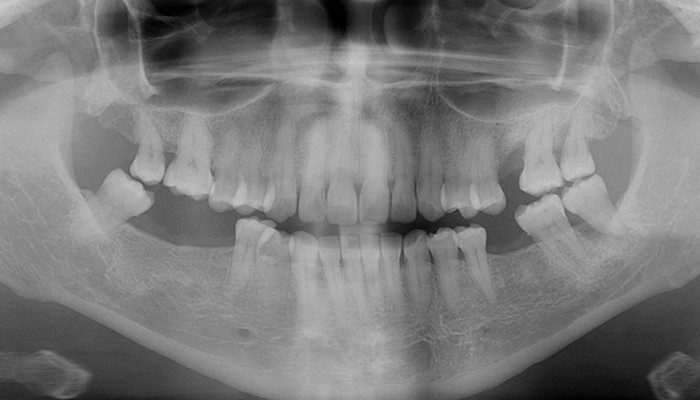

AVALIAÇÃO INICIAL

Na avaliação clínica observou-se ausência dos elementos 36, 46 e 47, com rebordo cicatrizado e atrofia de espessura. Ao exame radiográfico/tomográfico observou-se disponibilidade óssea para implantação e possibilidade de reabilitação em carga imediata com prótese provisória.

1 | Panorâmica inicial.